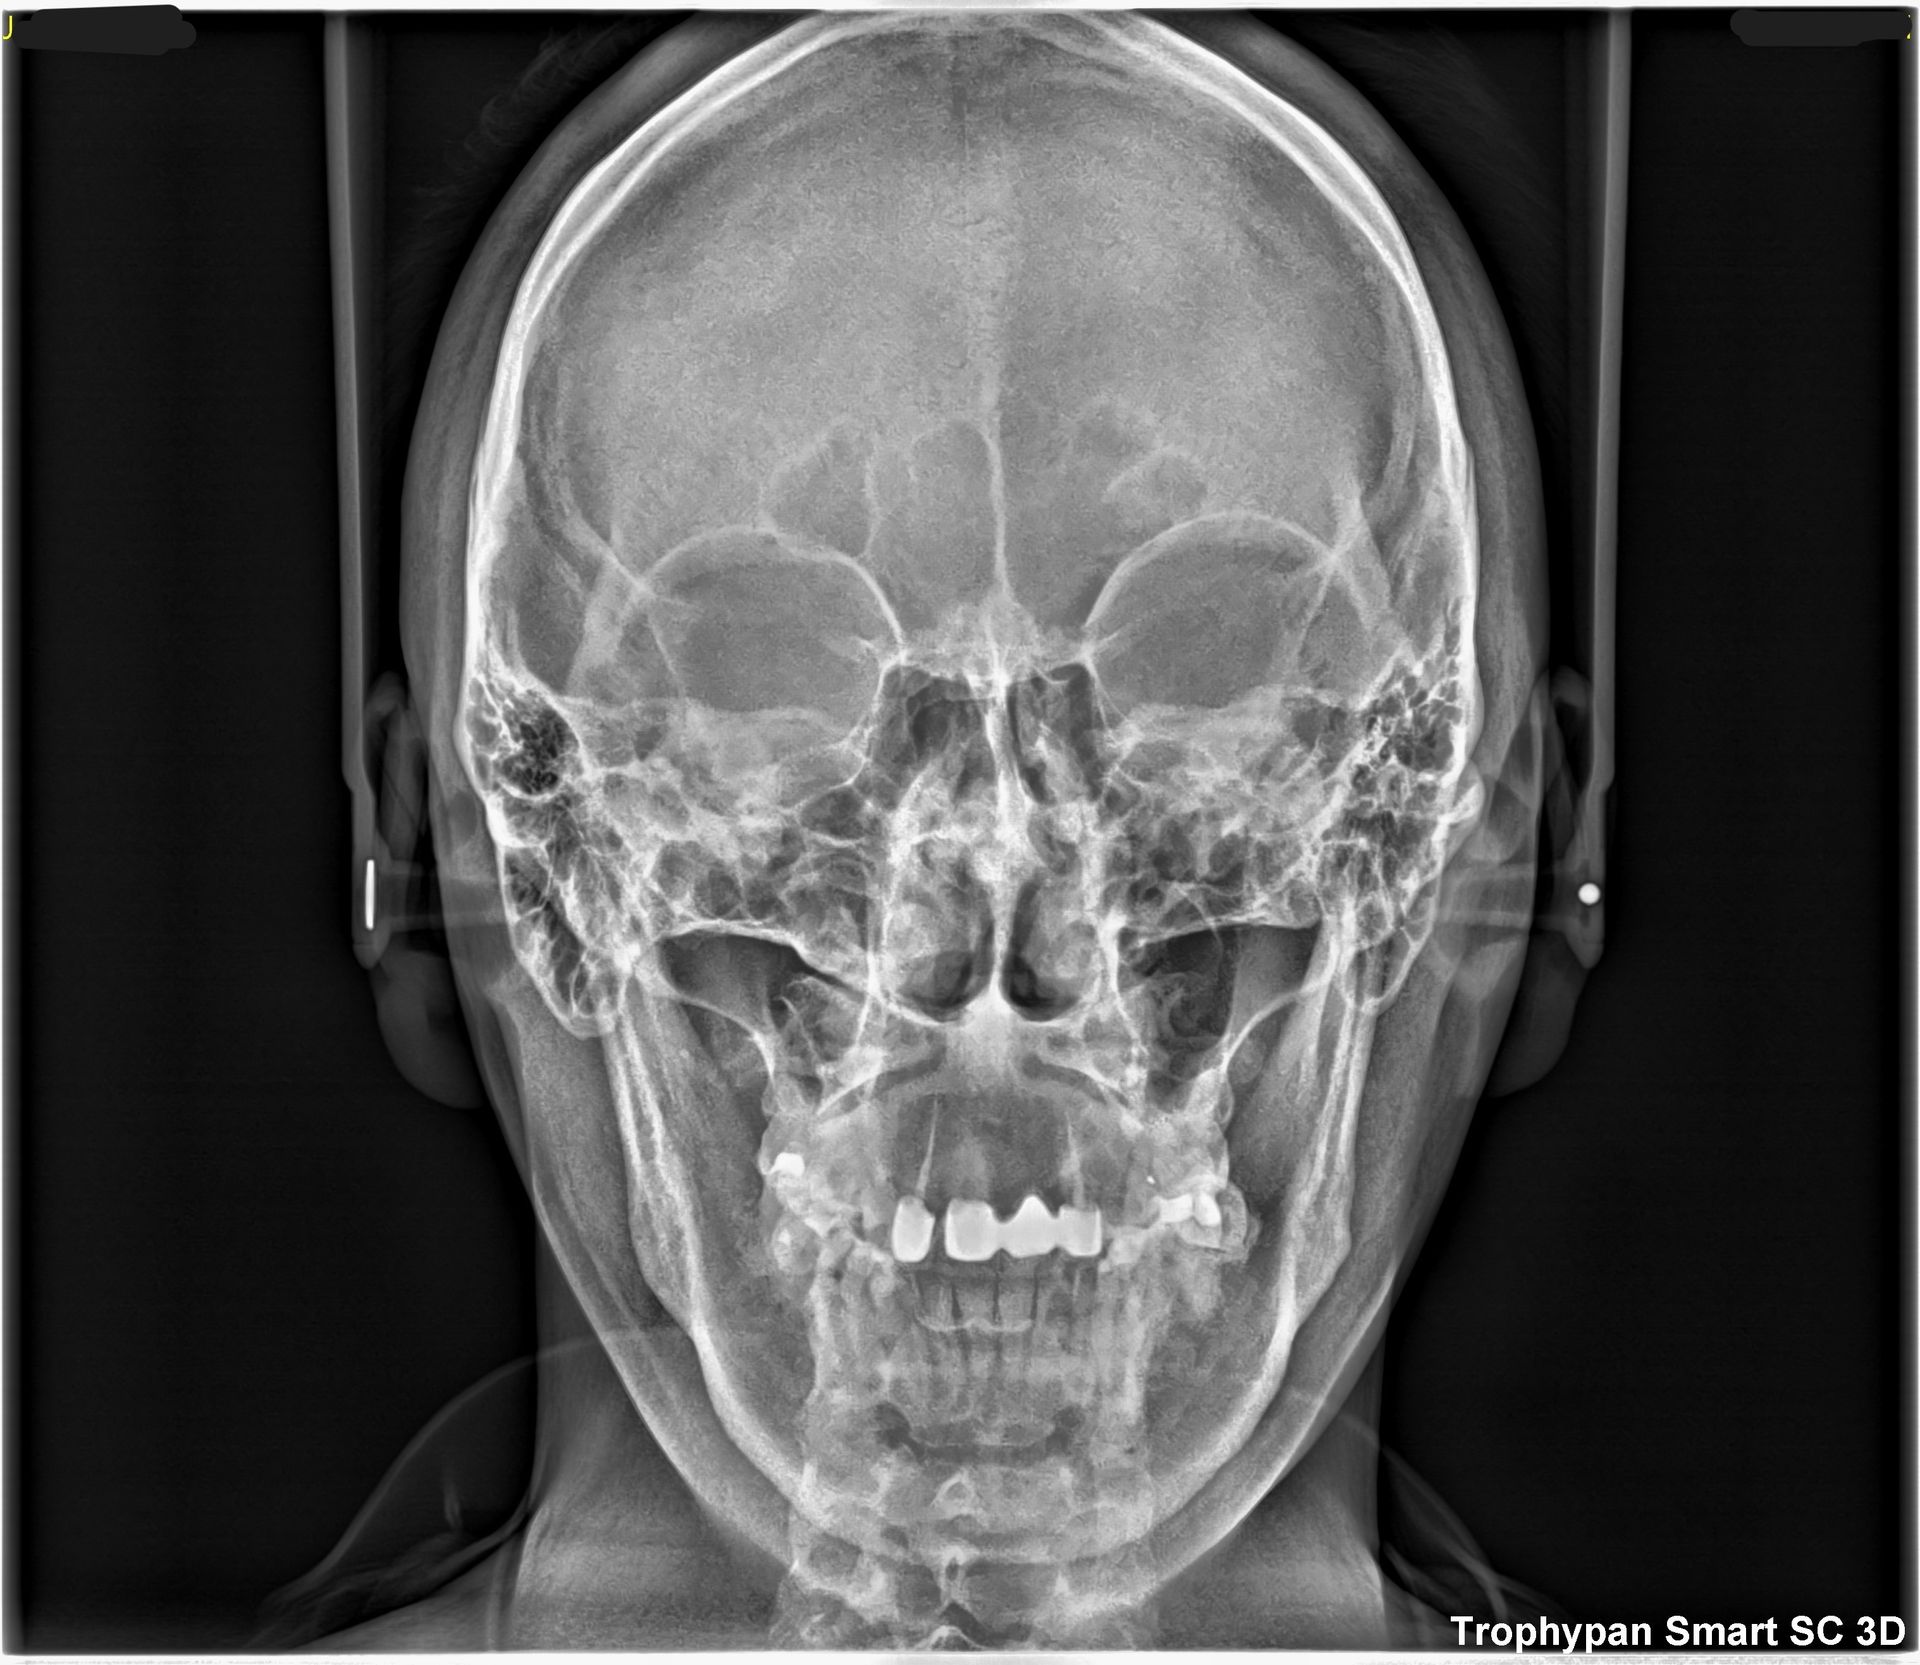

Uno de nuestros principales servicios es la adquisición de imágenes dentales 2D y 3D, fundamentales para un diagnóstico preciso y una planificación adecuada de tratamientos dentales.

Contamos con tecnología avanzada que nos permite obtener imágenes claras y detalladas de la boca y los tejidos circundantes, lo que es crucial para evaluar la salud dental y detectar posibles problemas.